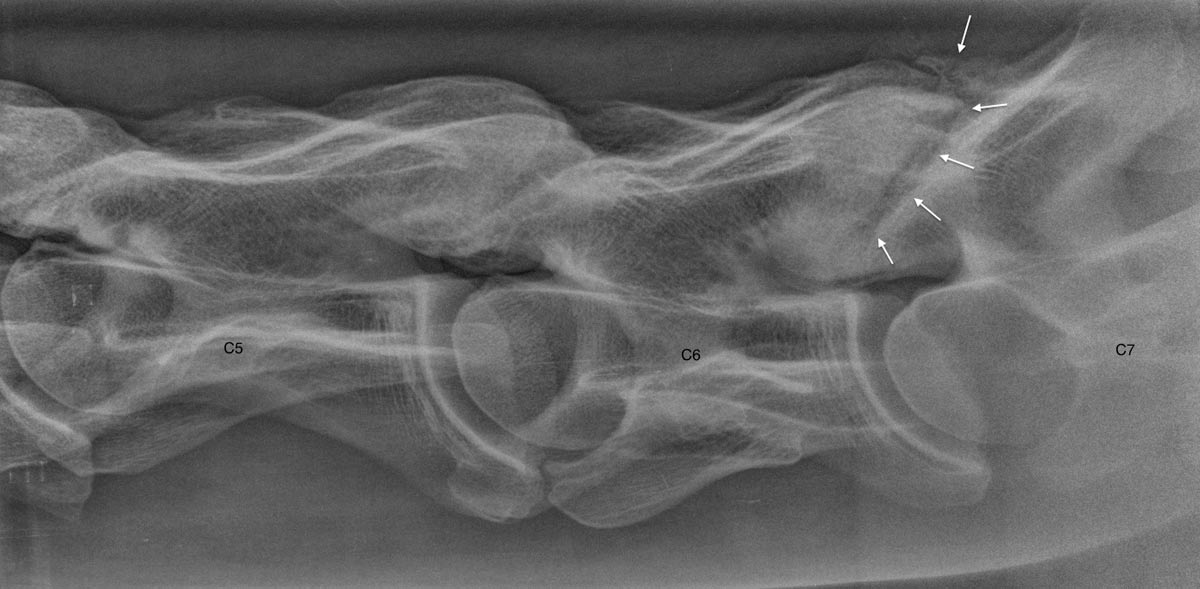

Radiology is an already long-lasting technique that is still a big evolution in this modern digital world. EquiSound features two digital radiography systems combined with a strong x-ray machine of 80.000 Watt (80 kV). We can make radiographs of excellent quality of the complete horse, including head, neck and back.